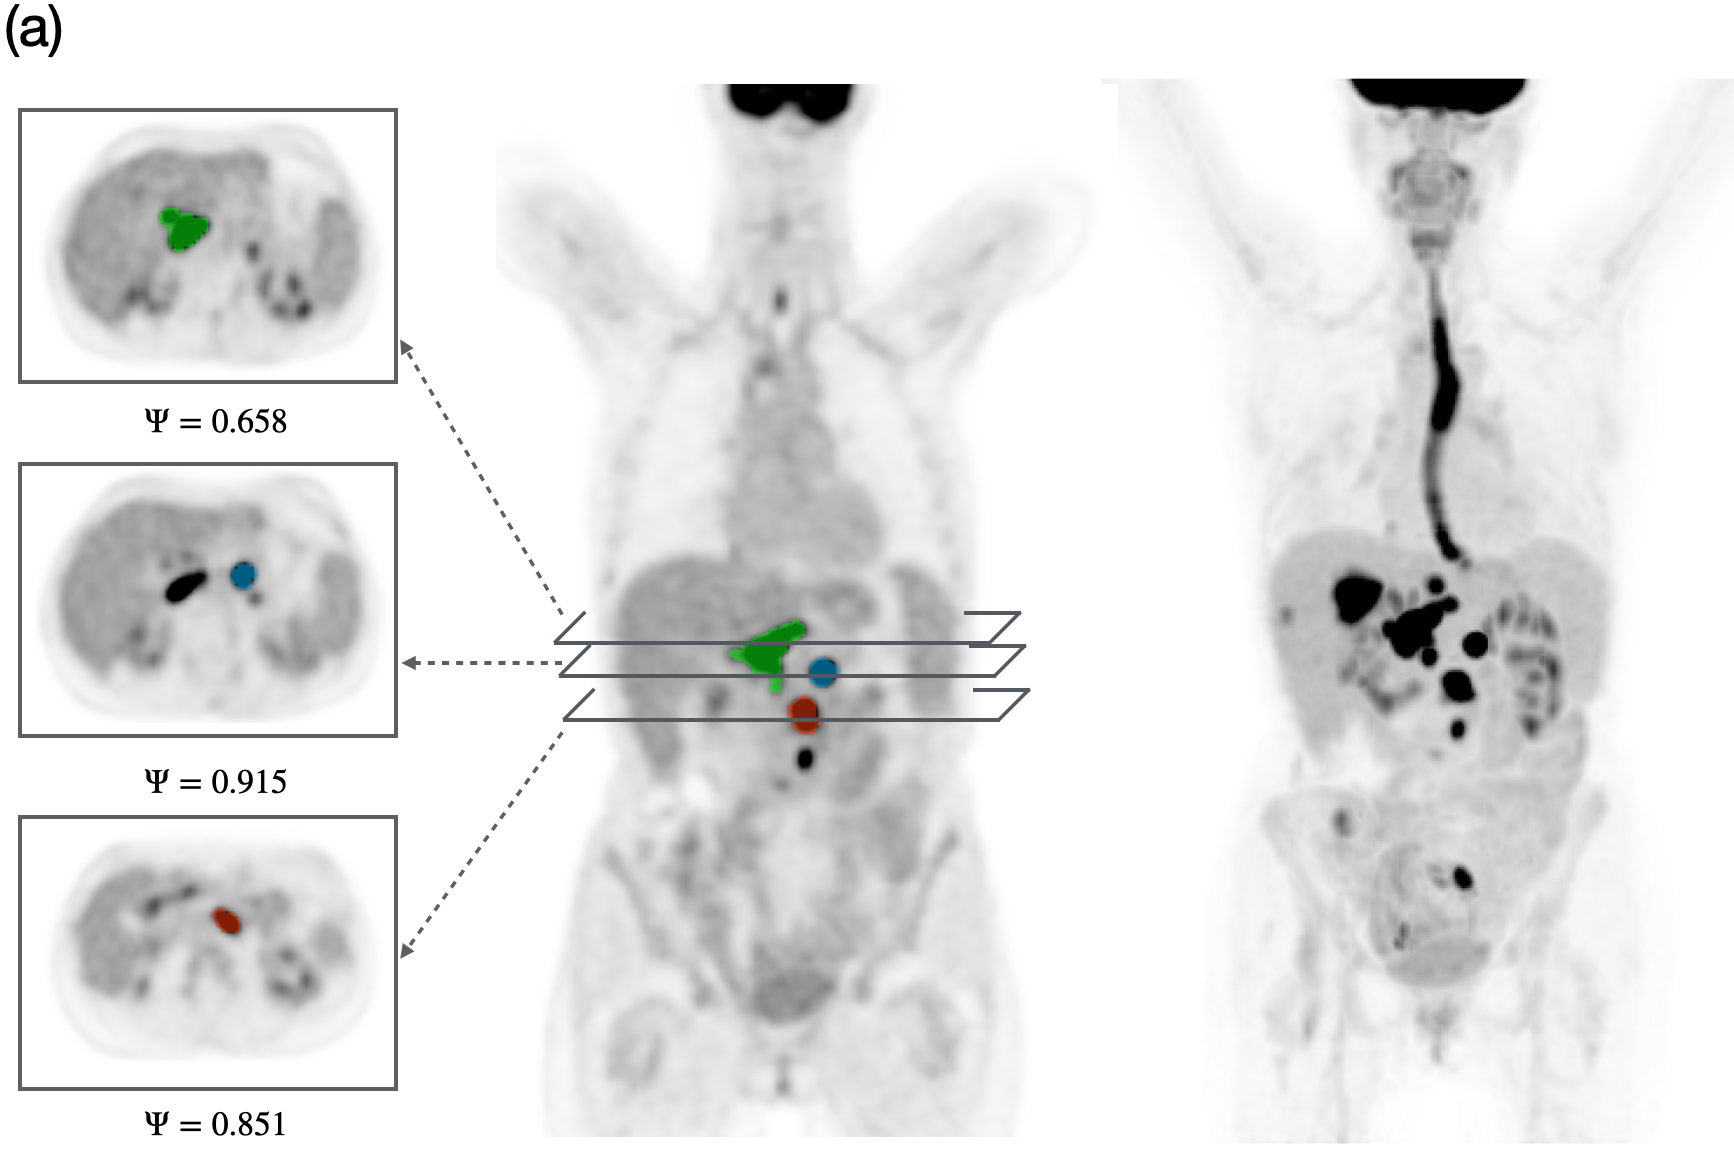

Details of model parameters, as well as their units and values used throughout this study are given in Table 2. We computationally studied the long-term outcome of the treatment by varying the tumor proliferation rate a𝑎aitalic_a and tumor lesion sphericity ΨΨ\Psiroman_Ψ within ranges estimated from literature and our own dataset. Figure 2 shows representative examples of sphericity values observed in 18F-FDG PET images of different lesions from lymphoma patients included in the study. This visualization highlights the morphological heterogeneity among lesions, suggesting that lesion geometry could be a potential factor influencing treatment response and long-term therapy outcome.

Refer to caption

Figure 2: PET/CT images of two different patients showing lesions with varying sphericity values (ΨΨ\Psiroman_Ψ). (a) 3D view of a full-body 18F-FDG PET scan of a lymphoma patient (rightmost image), with the coronal PET scan displaying three lesions of different sphericities, as shown in axial PET slices (leftmost images). (b) 3D view of a full-body PET scan of another lymphoma patient, with the coronal PET scan showing two lesions with different sphericities, along with several axial slices. Higher ΨΨ\Psiroman_Ψ values indicate more spherical lesions, while lower values correspond to irregularly shaped lesions.